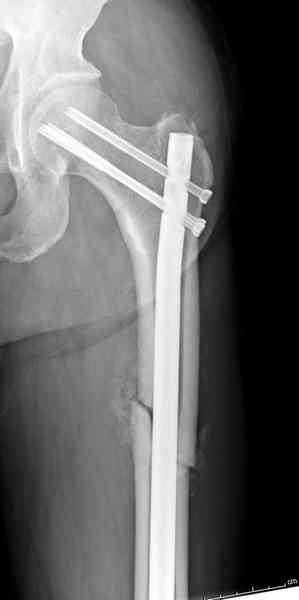

и проведены шурурпы через и спереди штифта без удаления.

Послеоперационные снимки